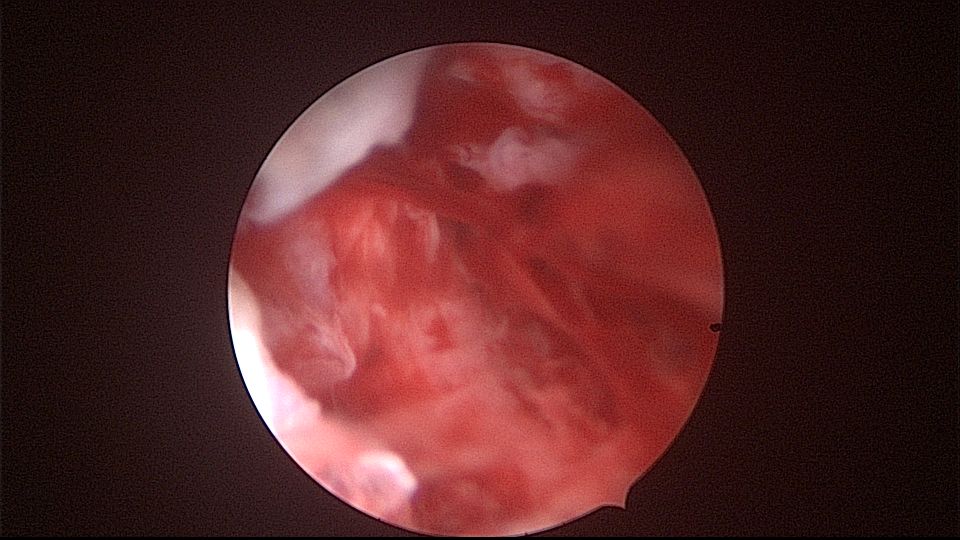

患者52岁,G2P1,顺产1次。安环27年,外院取环失败。病人肥胖,B超提示子宫前位,节育环距宫底0.9cm。子宫极度前倾前屈位,宫腔镜见宫颈管组织杂乱,宫颈管上段右前壁见假道,膨宫不良,视野模糊,寻找宫腔方向困难,准备B超监护过程中,拆走扩阴器,腹部下压子宫,终于寻找到了宫颈内口,看到了爱母环下端,异物钳牵拉出节育环,再次探查宫腔,无其他异常。